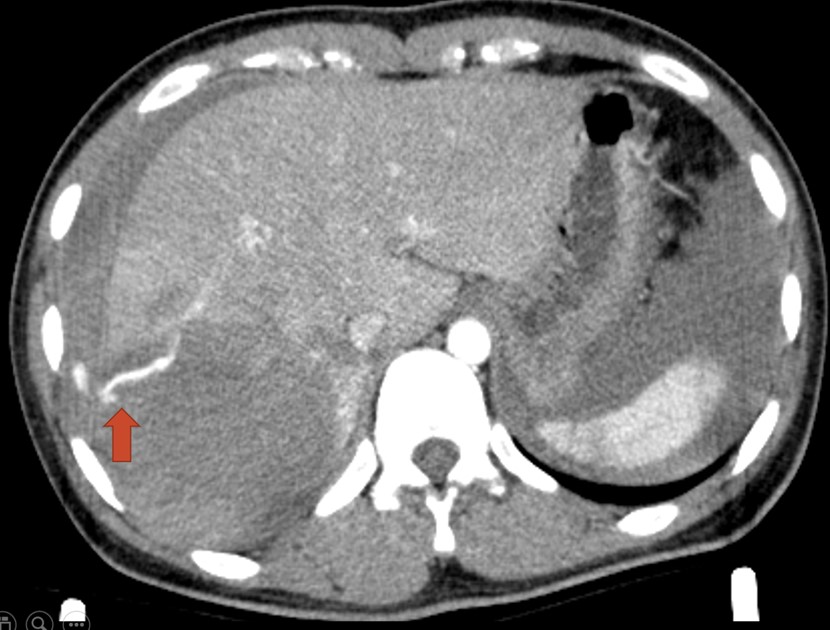

Hình 1. CLVT bụng thì động mạch thấy hình ảnh chảy máu tiến triển từ nhánh động mạch HPT VIII (mũi tên)